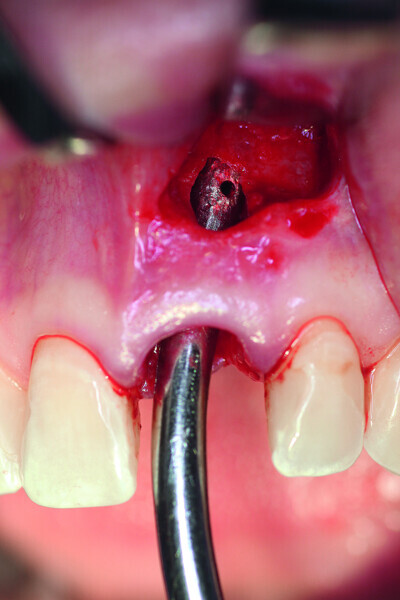

Fig. 3: After the extraction, the apical granulation tissue was excochleated.

Fig. 4: The implant site was uncovered after five months.